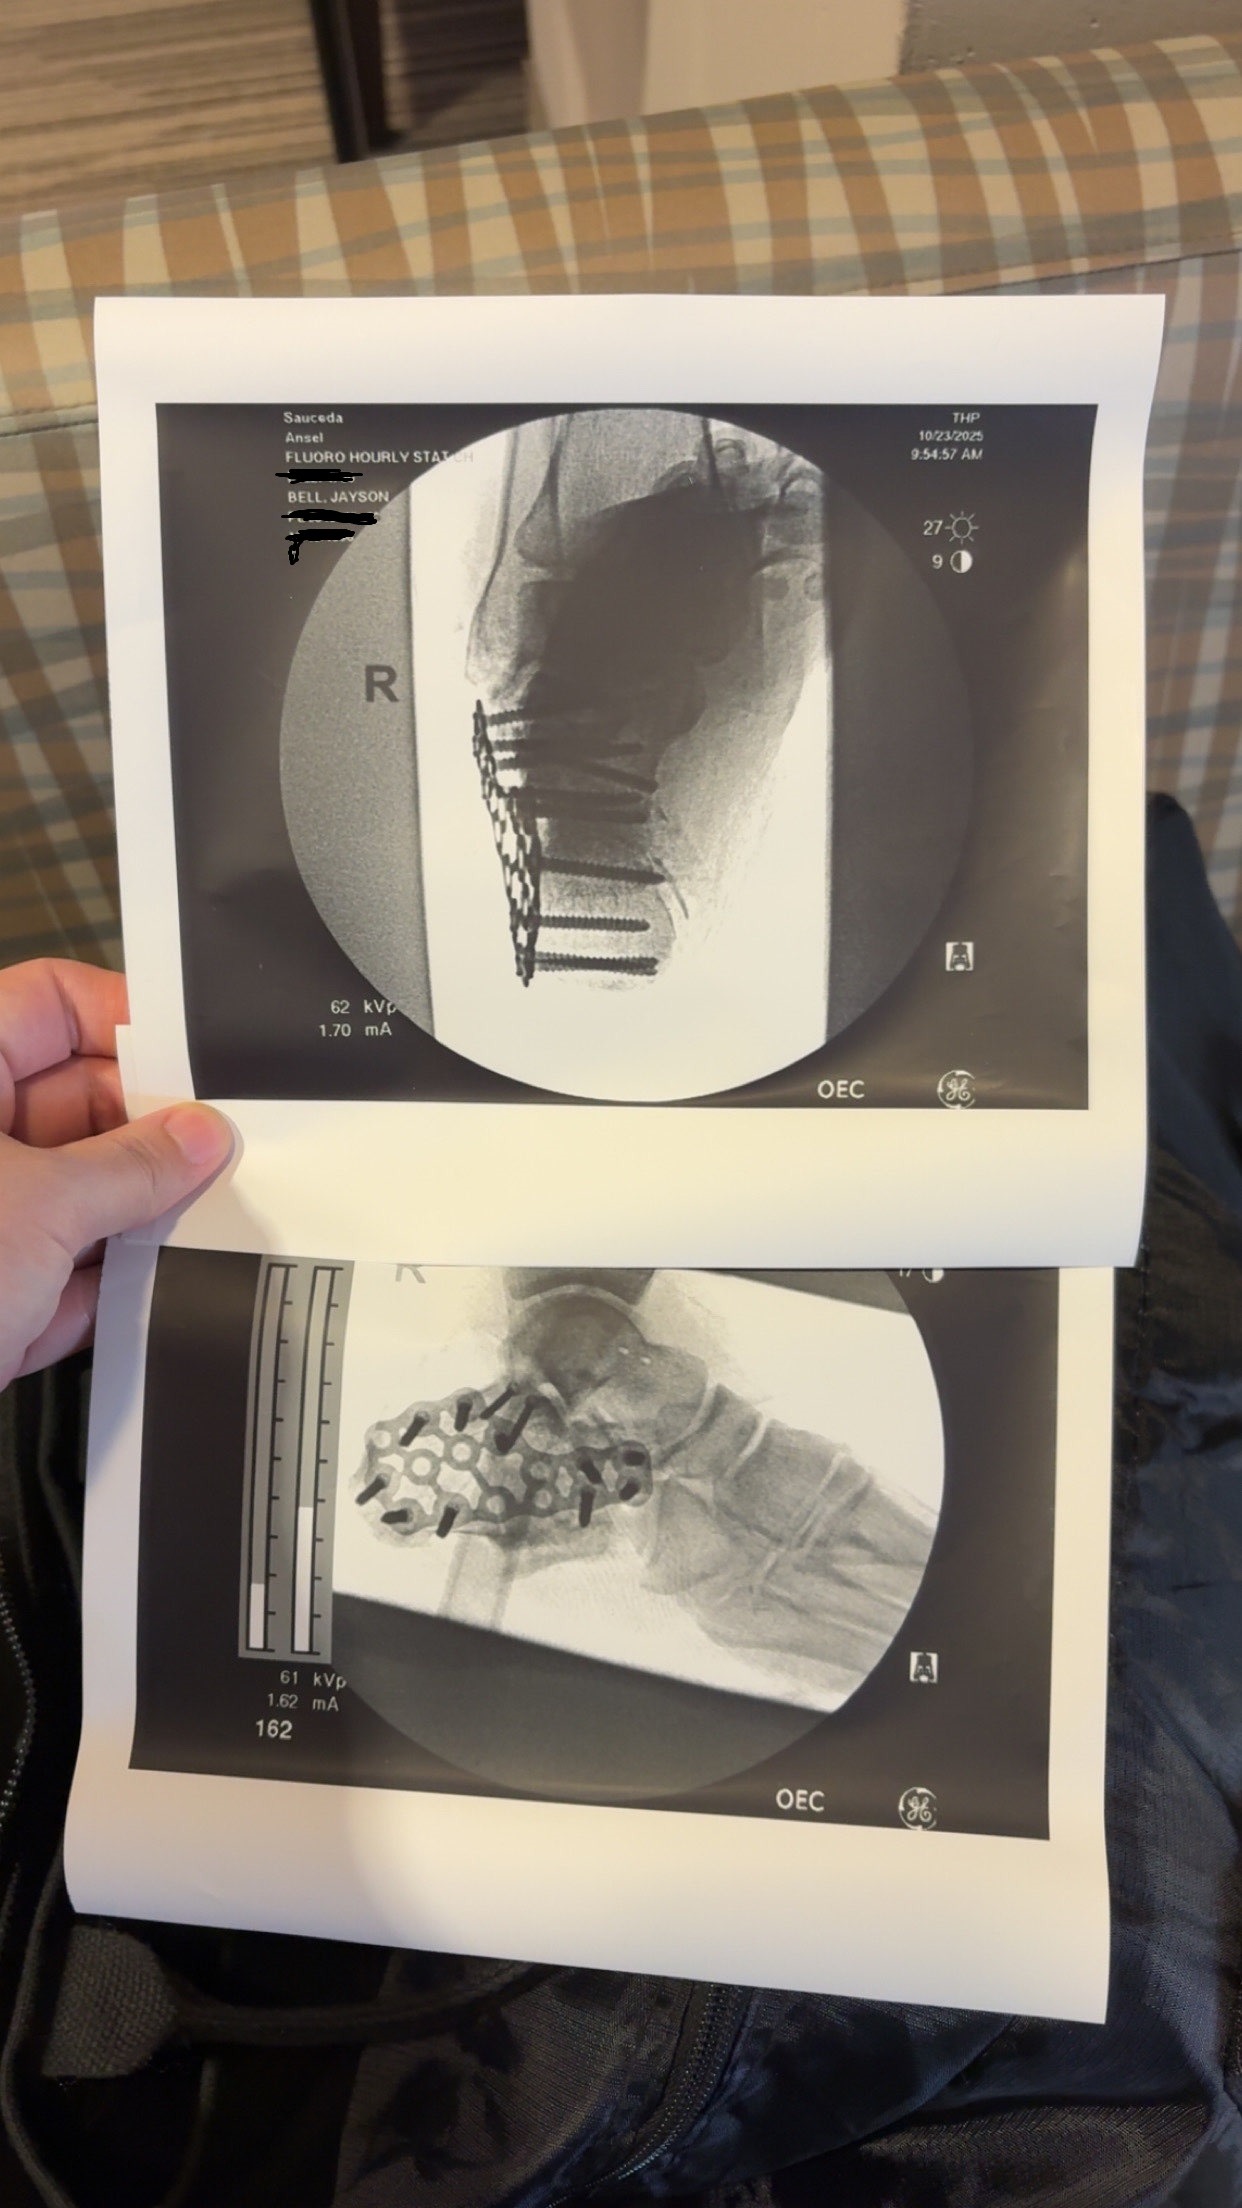

Other than totaling the bike, Ansel has scrapes and bruises across his arms, legs, and back. He has had to receive staples on the back of his scalp, surgery to clean a nasty laceration on his leg before stitching it closed, surgery to implant a metal plate and screws to his heel, physical therapy, and missed wages with our jobs as we navigate these new restrictions in our life. With the severity of what this accident has caused, we have decided to also seek out a lawyer to help file against the driver who hit him.